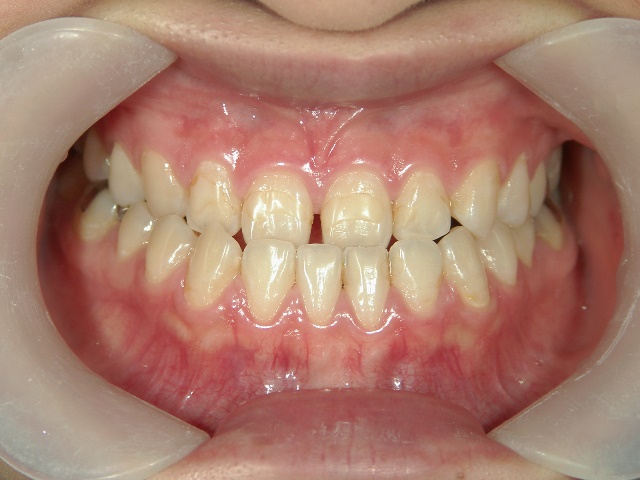

矯正歯科 治療後

no.31_7964_治療後_右 .JPGno.31_7964_治療後_正面 .JPGno.31_7964_治療後_左.JPG